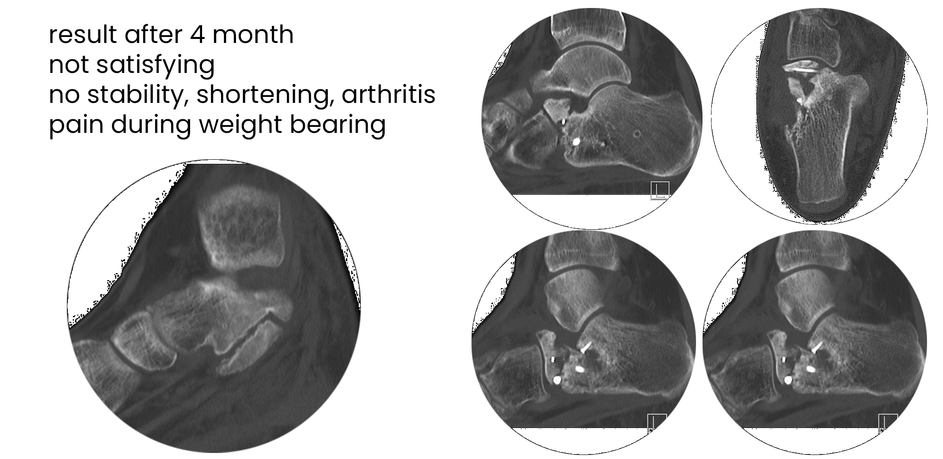

case 17LC, 29 years old, female, fall from horse

with the foot caught in the stirrup

"atypical fracture", surgery 19 hours after trauma